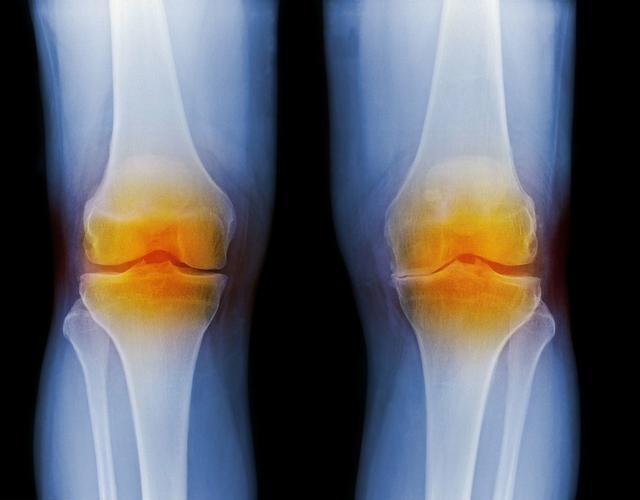

AS患者的关节病变较多,绝大多数首先侵犯骶髂关节,然后上行至颈椎。少部分患者先于颈椎或数个脊柱部分同时受侵犯,也可侵犯周围关节,早期病变部位关节有炎性疼痛,伴关节周围肌肉痉挛,强直感,晨起明显。还可以表现为夜痛,经活动或服用止痛剂后缓解。随病程发展,关节疼痛减轻,而脊柱各节段及关节活动受限、畸形,晚期,整个脊柱及下肢成硬弓,前屈。

5.大约一半AS患者患有短暂急性周围关节炎,大约25%患有永久性周围关节损伤。通常发生在大关节,下肢多于上肢。当累及肩部时,关节活动受限,疼痛更明显,梳头、抬手等动作也受限。而侵犯膝关节时,关节则呈代偿性弯曲,使行走、坐立等日常活动更加困难。肘,腕,脚的关节很少受到伤害。